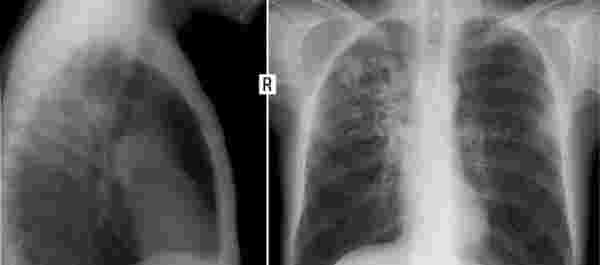

這事要從2019年說起,當時王大爺被診斷出肺部有結節,大小在1cm左右,醫生建議他保守治療。隨即醫生了解到王大爺的生活習慣很差,每天要抽一包香煙,于是醫生告誡他如果再繼續抽煙,那么這處結節就有可能演變為肺癌。

除此以外,茶煙是茶葉的提取物,因此它和煙草屬于類似的干葉物質,那么這種東西燃燒后一定會產生煙霧,煙霧的主要成分是可吸入顆粒物,大約是PM2.5-PM10,這都是肺部能夠吸入的顆粒物。

當這些固體顆粒物進入肺部后能完全堵塞肺泡,從而影響肺部的擴張,像上文的王大爺,本來就有肺結節,如果繼續吸茶煙,那么結節會越來越大,加快肺癌的進程。